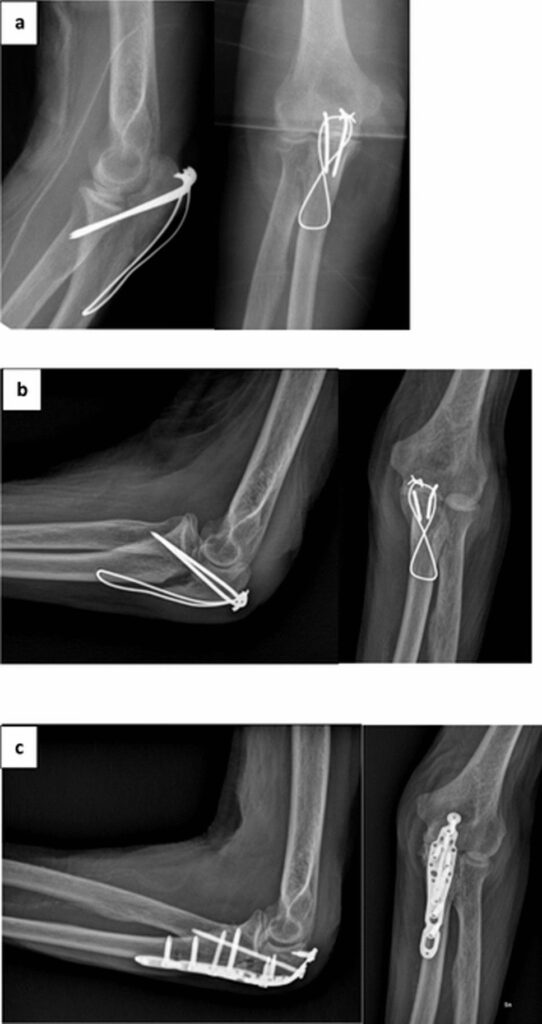

Standardbehandlingen for forskudte olecranonfrakturer har længe været operation. Målet med kirurgi er at opnå en anatomisk korrekt samling af knoglefragmenterne (reduktion) og stabilisere dem, så de kan hele (fiksering). De mest almindelige kirurgiske metoder omfatter:

- Tension-band wiring: En teknik, hvor ståltråde og pinde bruges til at komprimere brudstykkerne sammen.

- Pladefiksering: En metalplade skrues fast på knoglen hen over bruddet for at holde det stabilt.

For yngre, raske patienter er disse metoder yderst effektive og giver generelt gode resultater. Udfordringen opstår, når patienten er ældre, skrøbelig og har andre underliggende helbredsproblemer.